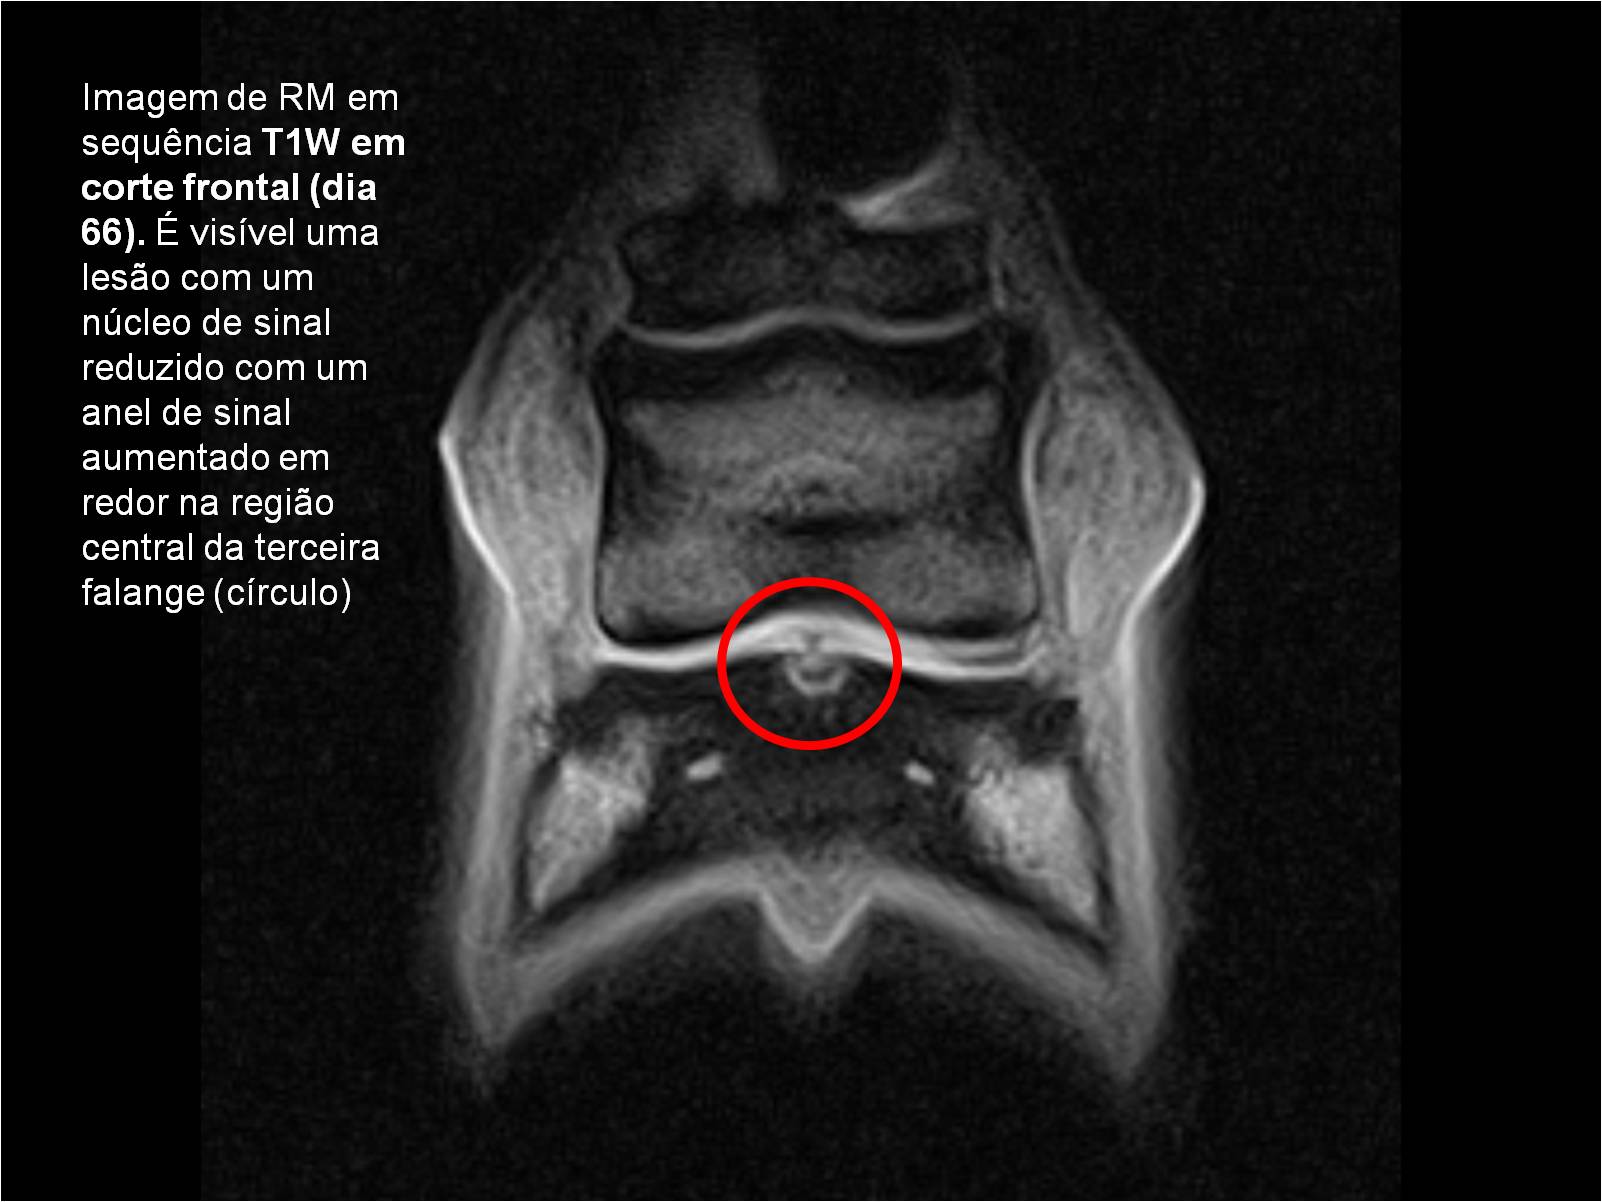

Publisher: Universidade de Évora

Abstract: O relatório de estágio encontra-se estruturado em três partes distintas. A primeira parte faz a caracterização das infraestruturas e funcionamento do Hospital Veterinário de Equinos de Lüsche, Oldenburg, Alemanha, assim como a análise casuística dos casos clínicos acompanhados durante os 6 meses de estágio. A segunda parte consiste de uma revisão bibliográfica sobre quistos do osso subcondral em equinos. Por fim, a terceira parte consta da apresentação e discussão de um caso clínico, nomeadamente o diagnóstico e acompanhamento imagiológico, por ressonância magnética, de um quisto subcondral na terceira falange num cavalo adulto; ### Abstract Equine Practice- Subcondral bone cyst of the third phalanx This internship report is divided in three parts. The first part characterizes the infrastructure and function of the Equine Hospital Lüsche, Oldenburg, Germany, as well as the casuistic of the clinical cases accompanied during the 6 month internship. The second part consists in a bibliographic review of cystic lesions of the subchondral bone in equines. The third part consists in a case report, the diagnostic and imagiological accompaniment, by use of magnetic resonance imaging, of a subchondral bone cyst in the distal phalanx of an adult equine.